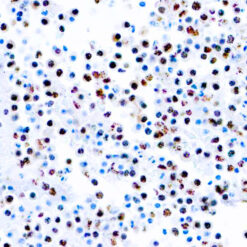

This antibody reacts with a 33-36 kDa protein known as ERCC1 (excision repair cross complementing) polypeptide. ERCC1 is required for nucleotide excision repair of damaged DNA and is homologous to RAD10. In mammalian cells, XPG cleaves 3’ of the DNA lesion while ERCC1-XPF complex makes the 5’ incision.

| Cellular Localization | Nuclear |

| Positive Control Tissue | Tonsil |

| Incubation & Temperature | 30 min @ RT |